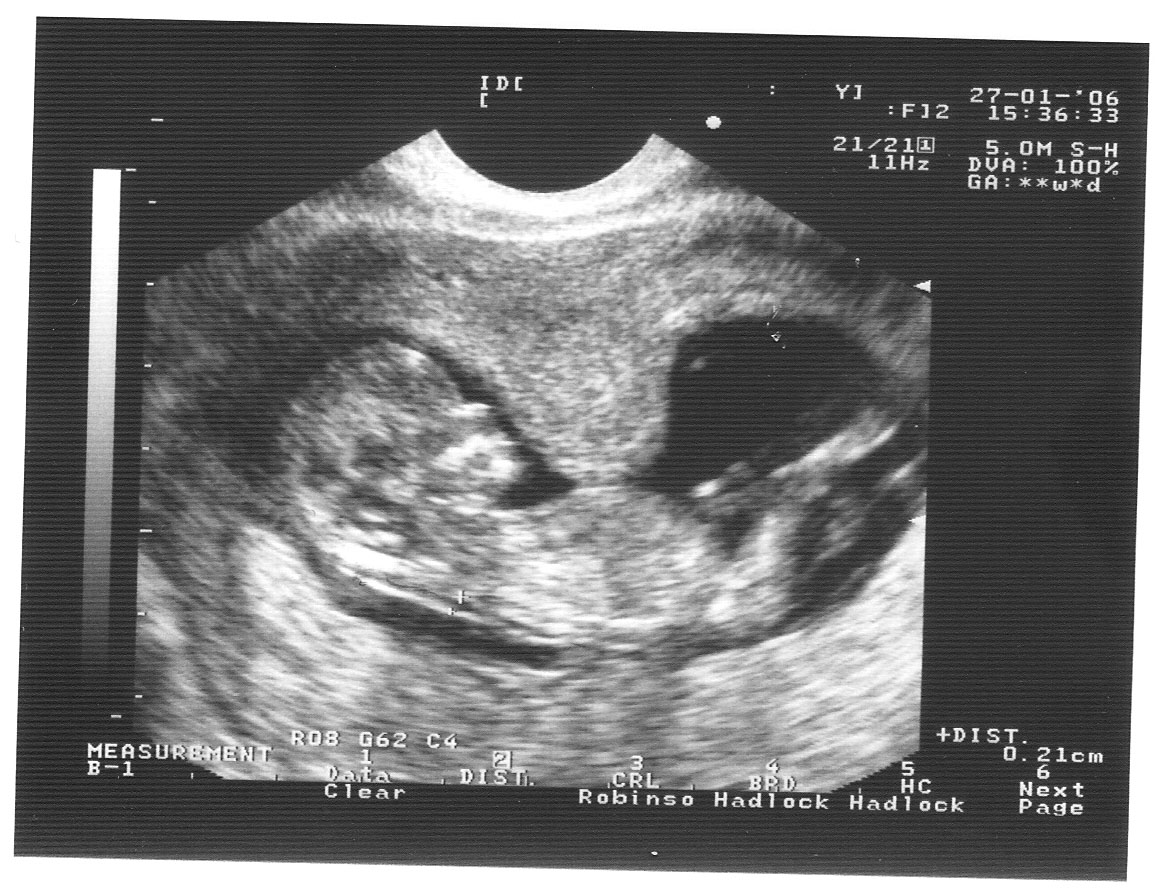

Узи при беременности на раннем сроке.

Информативность узи на ранних сроках беременности

Следите за регулярностью УЗИ, так как мониторинг состояния матки в динамике позволяет выявить возможные отклонения на ранних сроках.